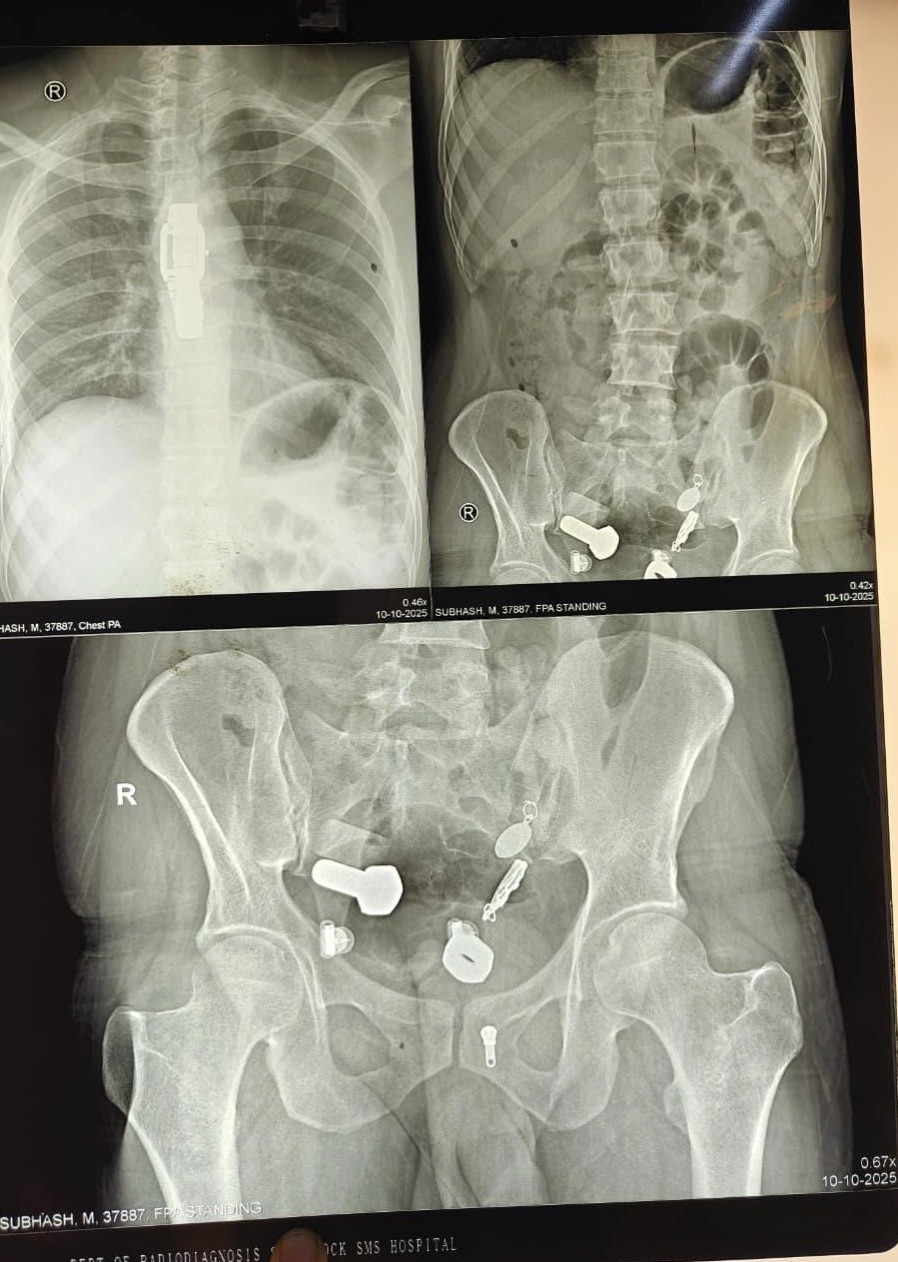

Родственники привезли 34-летнего мужчину в больницу, когда он почувствовал сильную боль в животе и не мог есть и пить. Сканирование показало, что в его пищеводе застряли часы, а в толстом кишечнике оказались металлические фрагменты, гайки и болты.

Врачи обнаружили целую коллекцию в животе пациента.

Хирурги попытались удалить предметы с помощью эндоскопии, но потребовалась полостная операция, она продлилась три часа.

Через небольшой разрез в брюшной полости хирурги извлекли часы и другие инородные тела.

Мужчина поступил в больницу Саваи Мансингх в Джайпуре, Индия, 9 октября. Сейчас он восстанавливается.